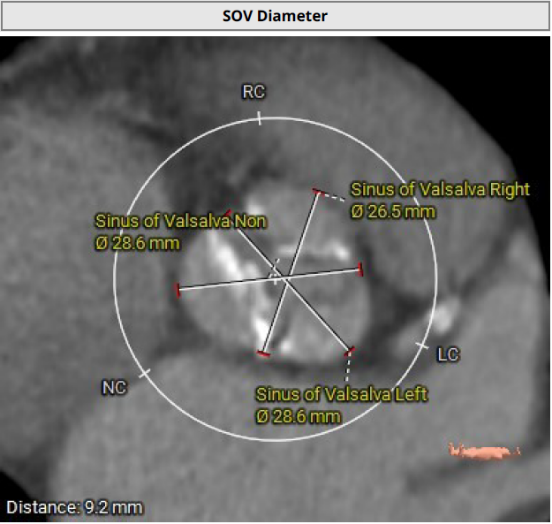

主动脉瓣瓣环及其他基本平面测量

主动脉瓣瓣上及瓣下多平面测量

经过医院多学科团队术前测量对病例深入分析,同时结合AI术前分析辅助决策软件进行三维和二维图像融合结果,指出本例难点/要点主要包括:

• 三叶式主动脉瓣,轻度钙化,瓦氏窦较小(直径约26-28mm),应注意瓣膜、预扩和/或者后扩球囊型号的选择;